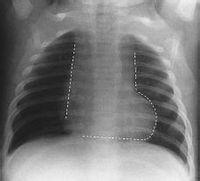

靴形心反映左心排血受阻伴右心室漏斗部發育不全。常見疾病見於主動脈瓣病變、高血壓、冠心病、心肌病或法洛四聯症。

主動脈瓣病變、高血壓、冠心病等所致靴形心病理生理改變以左心負荷增大,左室肥大,向左膨隆,心尖下移。法洛四聯症所致右心室肥大致肺動脈段- 心腰部凹陷, 心尖圓隆, 上翹, 心臟近似靴形 。

肺動脈段凹陷和心尖下移,主動脈結多增寬,形似靴形